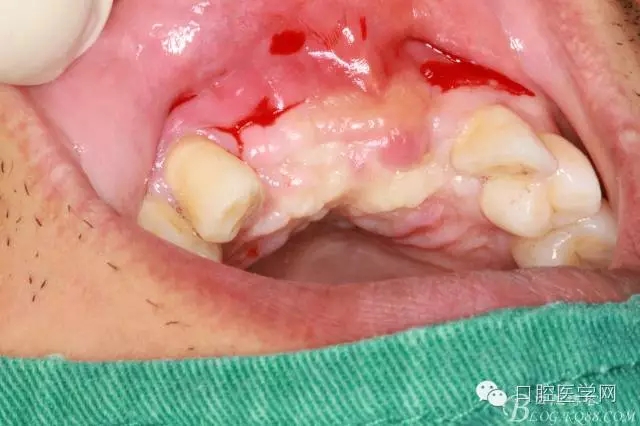

為他院轉診患者。男,無吸煙史,前牙因齲壞治療后,外力折斷導致拔除?,F拔除該牙后兩個多月。 左上區(qū)域骨寬度不足,計劃植入種植體同期GBR。

左上區(qū)域骨寬度不足,計劃植入種植體同期GBR。

植入種植體左側3510,右側4010,植骨Bioss,蓋膜Cytoplast。骨膜減張垂直褥式縫合加間斷縫合。

遺憾沒有保留術前口內照片,只有術后的。